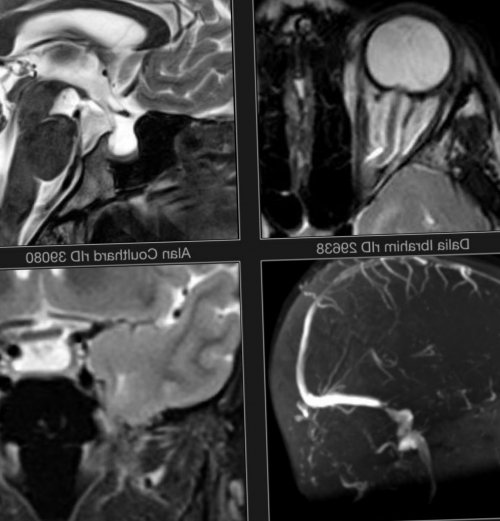

Внутричерепная гипотензия: КТ-исследования и их интерпретация

Раздел: Образы вокруг